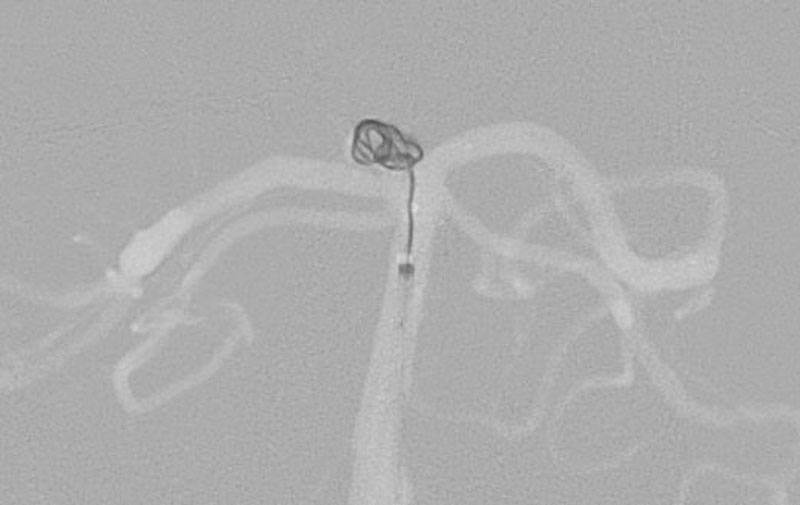

No.1591 手術中

No.1591 手術後

硬膜動静脈瘻

50代

救急外来